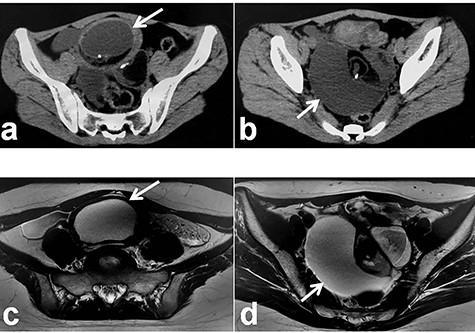

Patient 3: In a 13-year-old girl with abdominal pain, plain CT revealed bilateral ovarian tumors (Fig. 5a: left tumor and Fig. 5b: right tumor). Further examination, including MRI, revealed bilateral ovarian MCTs (Fig. 5c: left tumor; 77 cm × 70 cm, Fig. 5d: right tumor; 115 cm × 90 cm). During laparoscopic surgery, torsion of the left ovarian tumor was released, and each mass was placed in a specimen retrieval bag and removed (left tumor, Fig. 6a–d; right tumor, Fig. 6e–h). Both tumors were large, and content spillage was recognized during surgery. Peritoneal lavage was performed using large amounts of warmed fluid. Pathologic examination of both tumors confirmed the diagnosis of bilateral MCTs. The patient has been doing well without evidence of recurrence. She subsequently established a regular menstrual cycle.

Radiologic findings in Patient 3; (a): Plain CT showing the left-sided tumor (white arrow); (b): Plain CT showing the right-sided tumor (white arrow); (c): MRI showing the left-sided tumor (white arrow); (d): MRI showing the right-sided tumor (white arrow).